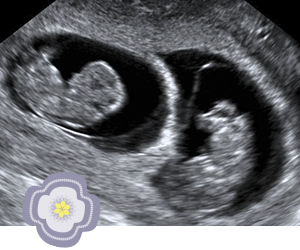

Tweeling of meerling

Tijdens een controle klopt er meer dan één hartje. Een leuke verrassing of misschien moet je wel even slikken.